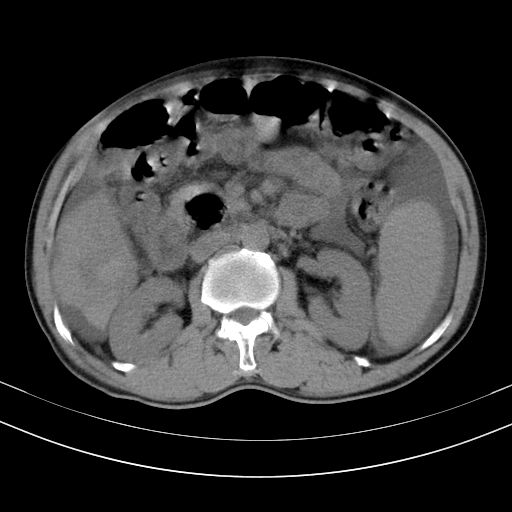

以下是引用随光逐影在2010-2-28 10:23:00的发言:[br]1)考虑肝癌;建议行ct增强扫描检查。2)肝硬化,脾大,腹水。3)慢性胆囊炎。

以下是引用dyqct在2010-2-28 16:44:00的发言:[br][quote]以下是引用随光逐影在2010-2-28 10:23:00的发言:[br]1)考虑肝癌;建议行ct增强扫描检查。2)肝硬化,脾大,腹水。3)慢性胆囊炎。